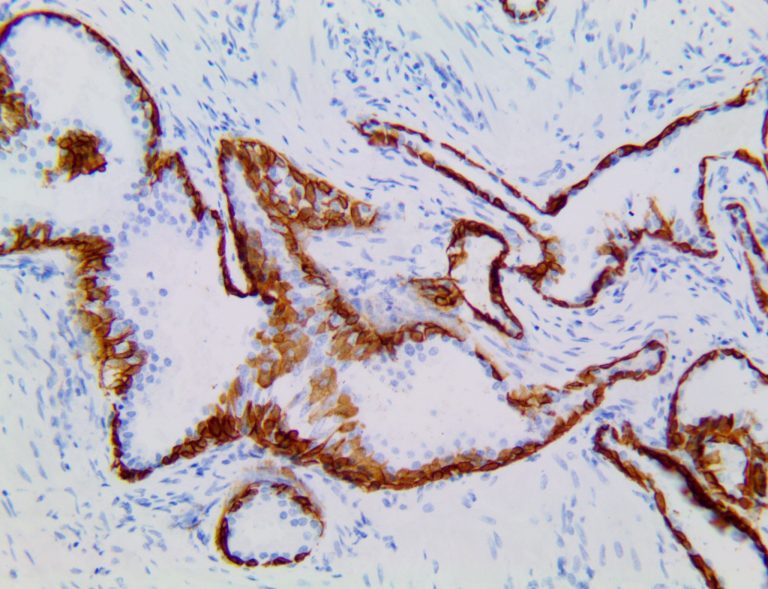

This activation induces inflammatory monocytes to highly express IL-6, starting a localized and then systemic cascade effect that results in hyperproduction of IL-6, which accelerates the inflammatory process. Because IL-6 also increases vascular permeability, excessive levels cause blood vessels to become very leaky. This, along with clotting factors released from vascular endothelial cells, stimulates the coagulation cascade, resulting in microthrombosis (tiny clots), which leads to ischemia and tissue death of the kidney, intestines, heart, liver, brain and extremities.